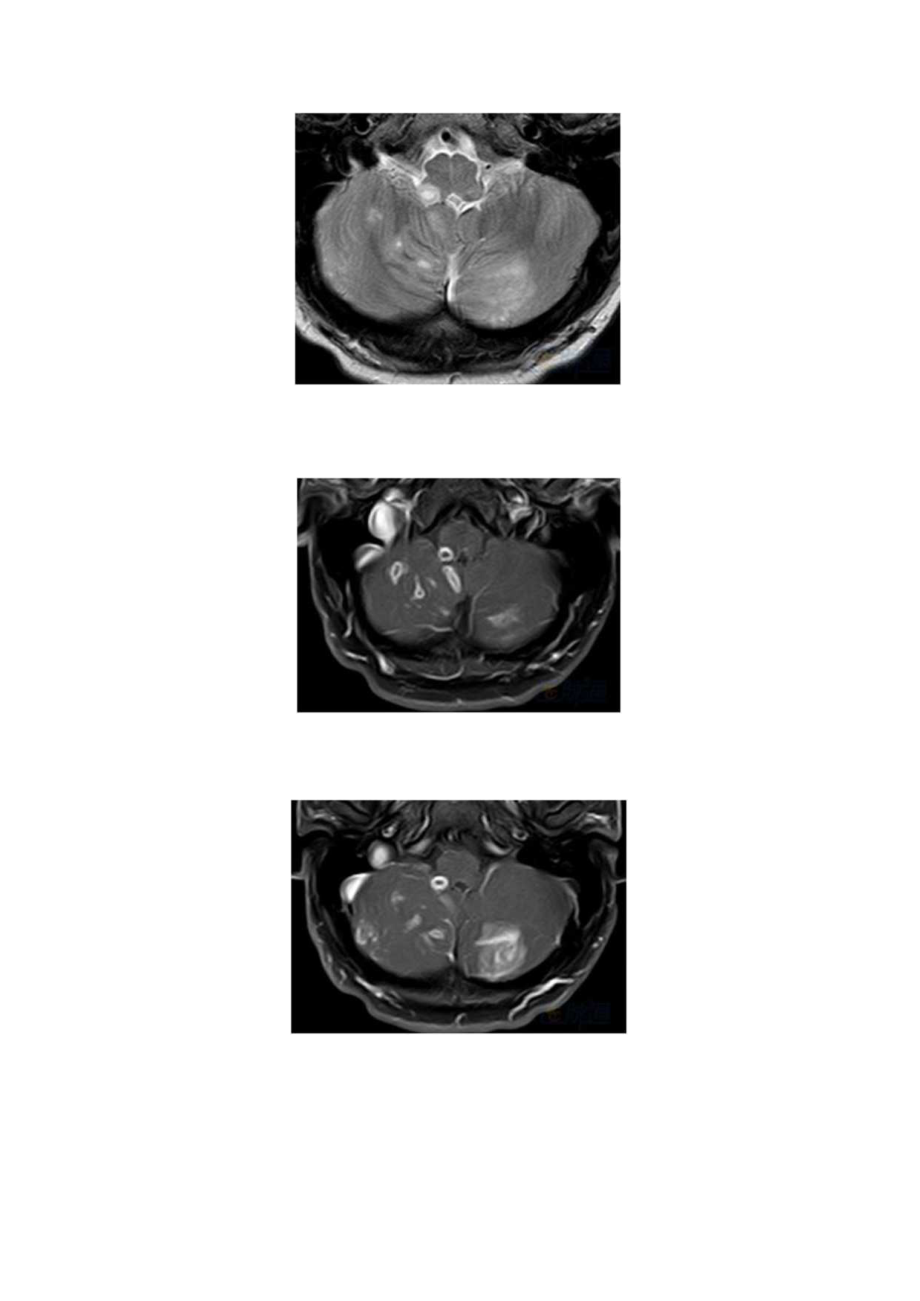

1、医学影像科一例李斯特菌菱脑炎(脑干脑炎)病例分析专题报告病史患者男性,29岁,发热,乏力和头痛加重一周,伴相关眩晕,共济失调,吞咽困难,复视,持续性呃逆,左面部感觉异常。读片分析轴向T1.WI(A)显示右延髓结节性Tb低信号病变。轴向T2WI(B,C)显示蚓部和两个小脑半球双边斑片状假结节性T2高信号。对比增强饱和脂肪TIW1.(D,E)显示脑干和小脑多发结节状和环状增强病变。左小脑半球也可见脑膜强化片状区域。轴向DWI(F)显示右侧延髓背索局限性扩散。诊断:李斯特菌菱脑炎(脑干脑炎)李斯特菌病是进食受李斯特菌污染的食品引起的一种严重感染。这种细菌可见于各种食物,如生肉,蔬菜和未经高温消毒牛奶